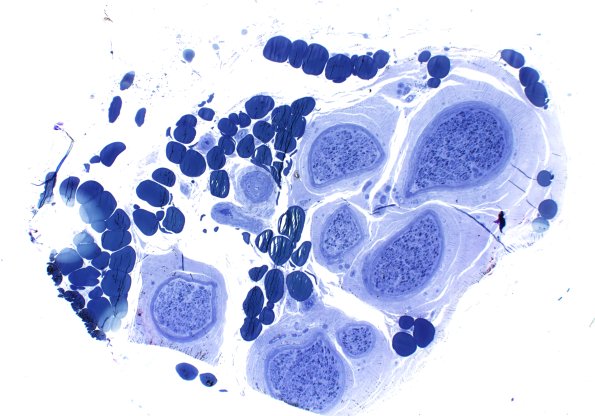

Case 15 History ---- The patient was a 79-year-old man with sensory motor polyneuropathy. He is not diabetic (HbA1c = 5.5). Operative procedure: left deltoid muscle biopsy and left sural nerve biopsy. ---- 15A1 One micron-thick, toluidine blue stained sections show moderate loss of large and small myelinated axons. Some remaining large axons show thin for axon caliber myelination, consistent with a history of injury and completed repair. Regenerative clusters are frequent. (plastic sections)